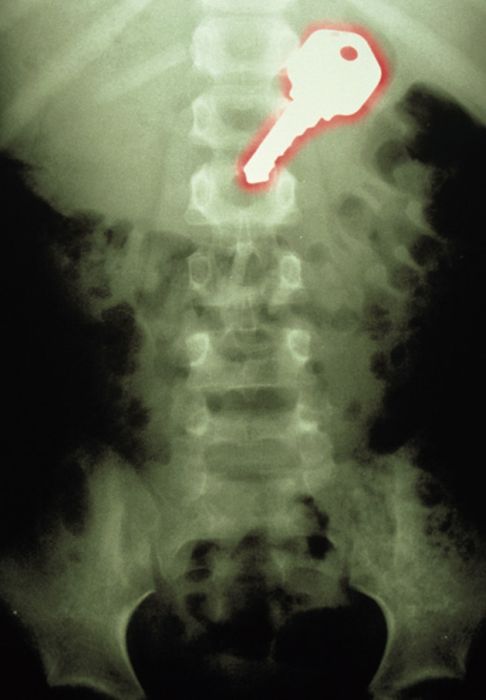

Рентгеновские снимки людей, которые умудрились сами или с чужой помощью разместить внутри своего организма разные посторонние предметы. От вилок и ножей до пуль и бензопилы (!!!). По этическим соображениям обычные снимки таких травм и повреждений выкладывать нельзя, зато рентгеновские можно – на них травмы видны достаточно условно, хоть и очень понятно.